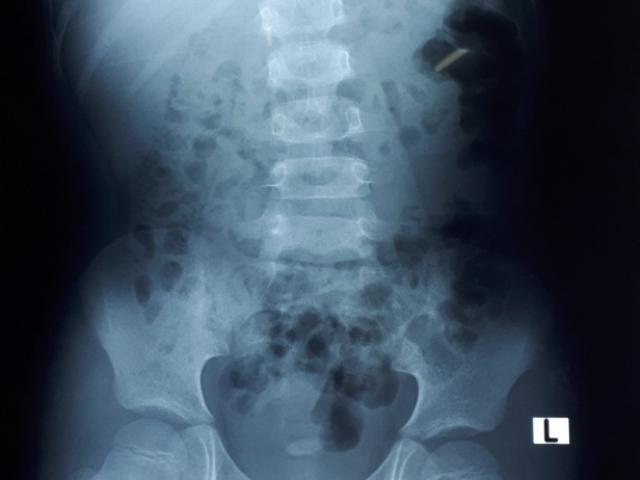

Mẹ “tá hỏa” khi bác sĩ phát hiện đầy sỏi trong thận của con trai 8 tuổi